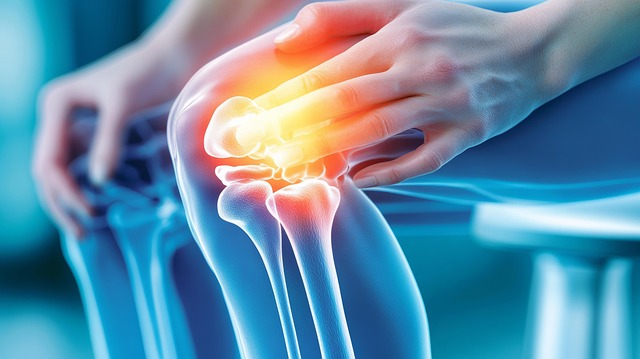

콘드로이친은 관절 연골의 주요 구성 성분으로, 골관절염 증상 완화에 도움을 주는 건강 보조제입니다. 임상 연구를 기반으로 한 정확한 콘드로이친 복용법을 알아보겠습니다.